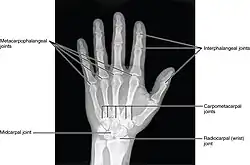

Les articulations interphalangiennes de la main sont les articulations qui unissent les phalanges de la main.

Chaque doigt, sauf le pouce, possède deux articulations interphalangiennes :

- une articulation interphalangienne proximale entre la phalange proximale et la phalange moyenne,

- une articulation interphalangienne distale entre la phalange moyenne et la phalange distale.

Le pouce n'a qu'une articulation interphalangienne entre la phalange proximale et la phalange distale.